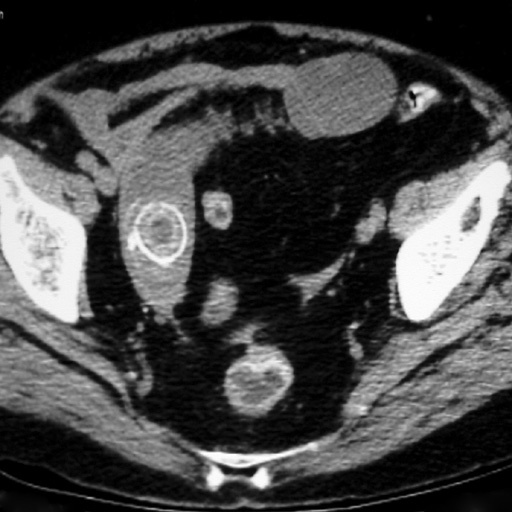

24

Q

Le patient a une diverticulite. Devant persitance fièvre et augmentation du sd inflammatoire à 48h on réalise le TDM suivant. Vu la taille de l’abcès (>5 cm on va dire), quelle CAT?

A

drainage de l’abcès: ponction percutanée écho ou scanno-guidée; OU drainage chirurgical si percut impossible (avec RDC à distance)